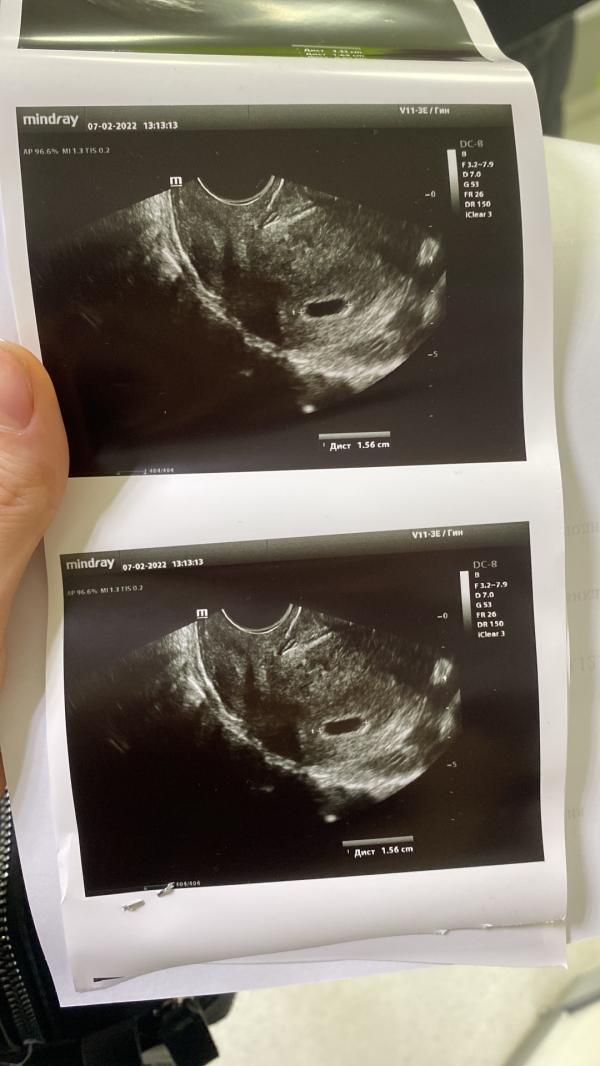

Девочки, подскажите, пожалуйста, у кого-нибудь было такое?! И чем закончилось?!

Сегодня нам 5 недель и 4 дня, пошли светло-коричневые выделения, побежала к врачу. Она сказала, что ничего страшного нет, но ей не нравится плодное яйцо:

Во-первых, там при таком ХГЧ (6616,3 - на 06.02.2022) уже должен быть желточный мешок, а его нет;

Во-вторых, сказала, что у меня форма плодного яйца свидетельствует о патологии. Неделю назад на узи плодного яйца не было вообще.

Беременность первая, страшно, не знае...